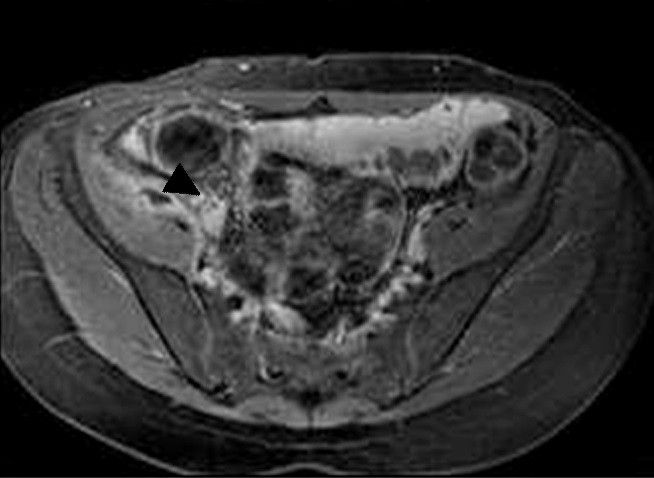

Figura 5

Enfermedad de Crohn

a y b) Secuencias T2 con saturación grasa en el

plano axial. Engrosamiento parietal circunferencial

de la última asa ileal sin edema que contacta con

el colon transverso presentando adherencias con

el mismo (flecha). Tracto sinusal que se extiende

desde el asa alterada al borde anterior del músculo

ilíaco derecho (flecha corta).

c) Secuencia T1 con

saturación grasa y gadolinio, pequeña colección

líquida en el espesor muscular con realce parietal

(punta de flecha)

Figura 6

Paciente de 39 años con enfermedad de Crohn

diagnosticada en 2012.

a) Sagital T2, el colon sigmoides presenta

disminución de calibre en la unión recto sigmoidea.

b) T2 axial, no hay evidencia de edema submucoso

ni otros signos de actividad. En la secuencia cine la

estenosis permanecía fija, por lo que se interpretó

como secuelar.